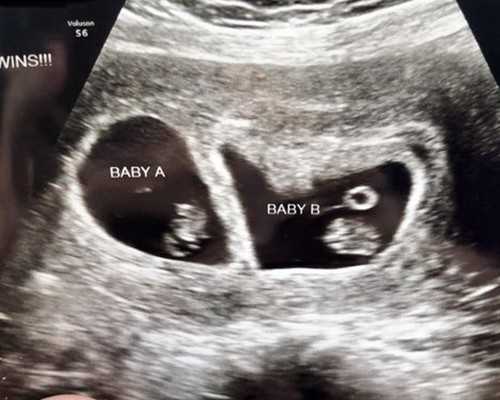

胎儿在母体内的生长发育非常快,怀孕后前8周,受精卵就由一个单细胞发育成有2亿个细胞的成型人体,此期称为胚胎;孕8周后即称为胎儿。怀孕6周时,胚胎的脊柱和脑部开始形成,心脏开始跳动,用B超就能测出胚胎和心脏的活动,此时孕妇可有早孕反应。7周后,四肢开始形成。8周后胚胎有了眼睛,但没有脸和外耳道;胚胎开始蠕动,但孕妇还感觉不到。12周时,胎儿大约有7厘米长,20克重,可看出人型,头与身体其他部位相比,显得较大。用多普勒听诊仪可听到胎心。经腹部在耻骨联合上方可摸到子宫底。